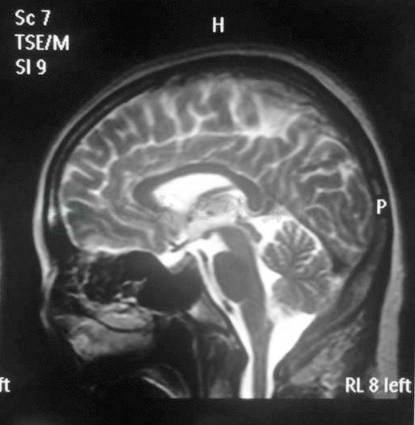

颅脑及颈部MRA及颅脑MRI平扫(2016年6月19日):左侧颈动脉近段迂曲,右侧颈动脉C1段小三角突起,考虑小动脉圆锥,右侧放射冠区缺血灶,鼻窦炎(图1)。

图23-1 颅脑及颈部MRA及颅脑MRI平扫

该患者为中年女性,病程短,起病急,生气为起病诱因,以恶心、呕吐、发热、消瘦为主要表现,抗感染、止吐治疗效果欠佳。入院查体言语欠清晰,双肺呼吸音粗,腹部查体未见异常,其余未见异常。辅助检查提示,白细胞增多,中性粒细胞比例升高,血沉及C反应蛋白及PCT升高,血钾降低,皮质醇降低;胃镜、肠镜、全消化道钡餐未见明显异常;腹盆CT示胆囊炎、轻度脂肪肝;颅脑及颈部MRA及颅脑MRI平扫示左侧颈动脉近段迂曲,右侧颈动脉C1段小三角突起,考虑小动脉圆锥,右侧放射冠区缺血灶,鼻窦炎。当地医院神经内科会诊考虑患者症状非神经系统疾病所致。